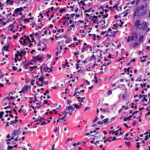

Histopathology. Typically, a dense perivascular infiltrate composed largely of neutrophils is seen assuming a bandlike distribution throughout the papillary dermis . Some of the neutrophils may show nuclear fragmentation (leukocytoclasis). In addition, the infiltrate may contain scattered lymphocytes and histiocytes and occasional eosinophils. The density of the infiltrate varies and may be limited in a small proportion of cases. Vasodilation and swelling of endothelium with moderate erythrocyte extravasation and prominent edema of the upper dermis are characteristic. In some instances, subepidermal blister formation may result. Extensive vascular damage is not a feature of Sweet’s syndrome. The histologic appearance varies depending on the stage of the process. In later stages, lymphocytes and histiocytes may predominate. Sweet’s-like neutrophilic dermatoses often show a similar histologic picture. However, the reaction pattern may on occasion be quite different, for instance, manifesting as deep subcutaneous localized suppurative panniculitis. The infiltrate of Sweet’s syndrome is not characteristic enough to exclude infection on histologic findings alone. As always, to arrive at the correct interpretation of a neutrophilic infiltrate, cultures need to be obtained and special stains need to be performed to exclude an infectious etiology. |